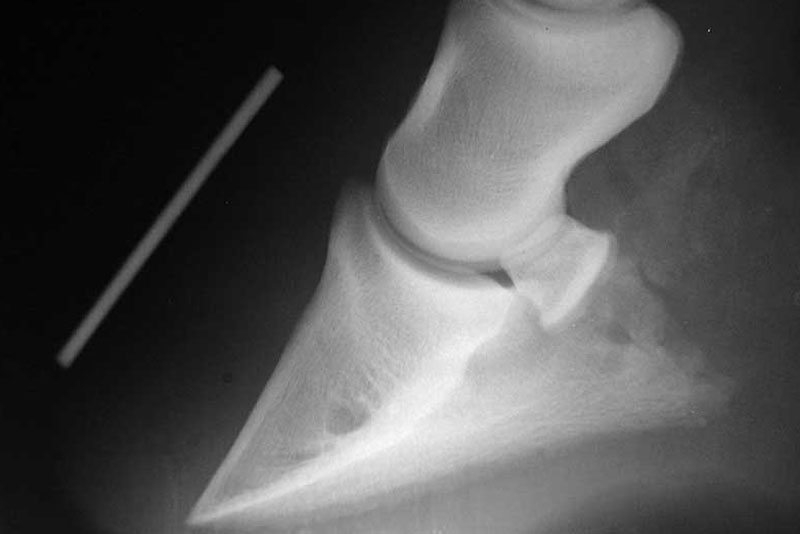

La situation évolue alors d'un cas de fourbure simple vers une forme plus aiguë, accompagné de la bascule de la phalange.

Les dégâts sont majoritairement situés dans les parties antérieures du pied, car sa vascularisation est plus importante dans cette partie.

Quand la fourbure est plus sévère, le cheval souffre du syndrome de l'affaissement, ou sinking, qui intervient lorsque le flux sanguin est interrompu au niveau de toutes les lamelles, sur une durée suffisamment longue, pour enfin toutes les détruire.

Dans ce cas, le squelette du cheval, qui n'est plus suspendu dans sa boite cornée, repose alors presque uniquement en appui sur la sole.